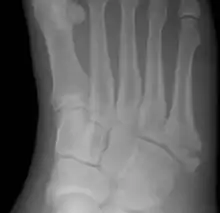

Jones fracture

A Jones fracture is a broken bone in a specific part of the fifth metatarsal of the foot between the base and middle part[8] that is known for its high rate of delayed healing or nonunion.[4] It results in pain near the midportion of the foot on the outside.[2] There may also be bruising and difficulty walking.[3] Onset is generally sudden.[4]

| Jones fracture as seen on Xray | |

The fracture typically occurs when the toes are pointed and the foot bends inwards.[6][2] This movement may occur when changing direction while the heel is off the ground such in dancing, tennis, or basketball.[9][10] Diagnosis is generally suspected based on symptoms and confirmed with X-rays.[3]

Diagnostic X-rays include anteroposterior, oblique, and lateral views and should be made with the foot in full flexion.